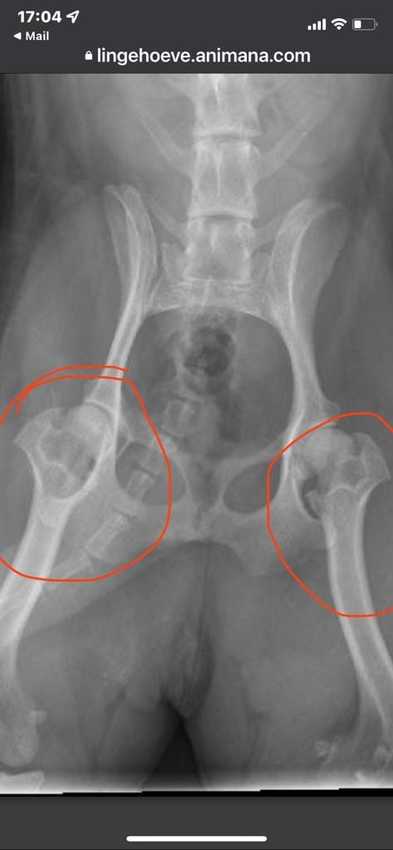

artrose heupkopjes zijn helemaal versleten en ze heeft nu injectie librela